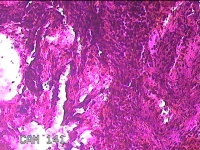

左侧鼻腔新生物

性别

女

年龄

43岁

临床诊断

1.慢性鼻窦炎 2.鼻息肉 3.鼻中隔偏曲 4.鼻腔粘连 5.变应性鼻炎

一般病史

鼻塞、脓涕3月余。’

标本名称

大体所见

灰白暗红色不规则肿物1.3x0.3x0.2cm一个,表面糜烂,内有少许骨质。